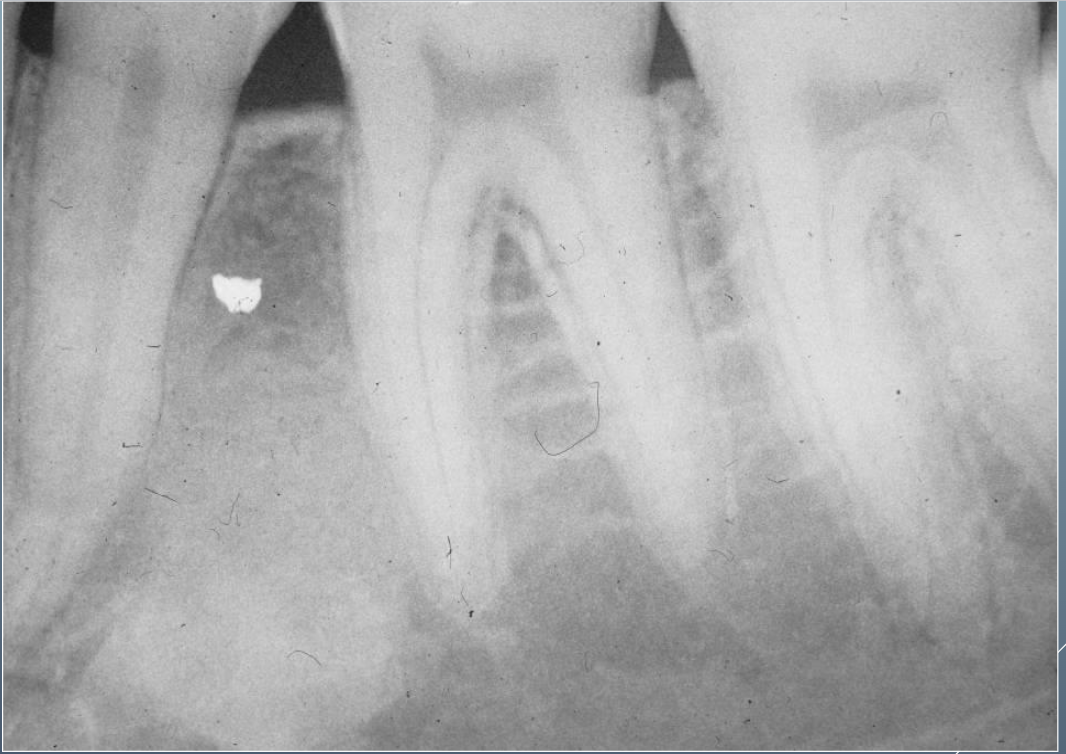

20

Q

WHAT’S THIS?

A

CONDENSING OSTEITIS

CHRONIC FOCAL SCLEROSING OSTEOMYELITIS